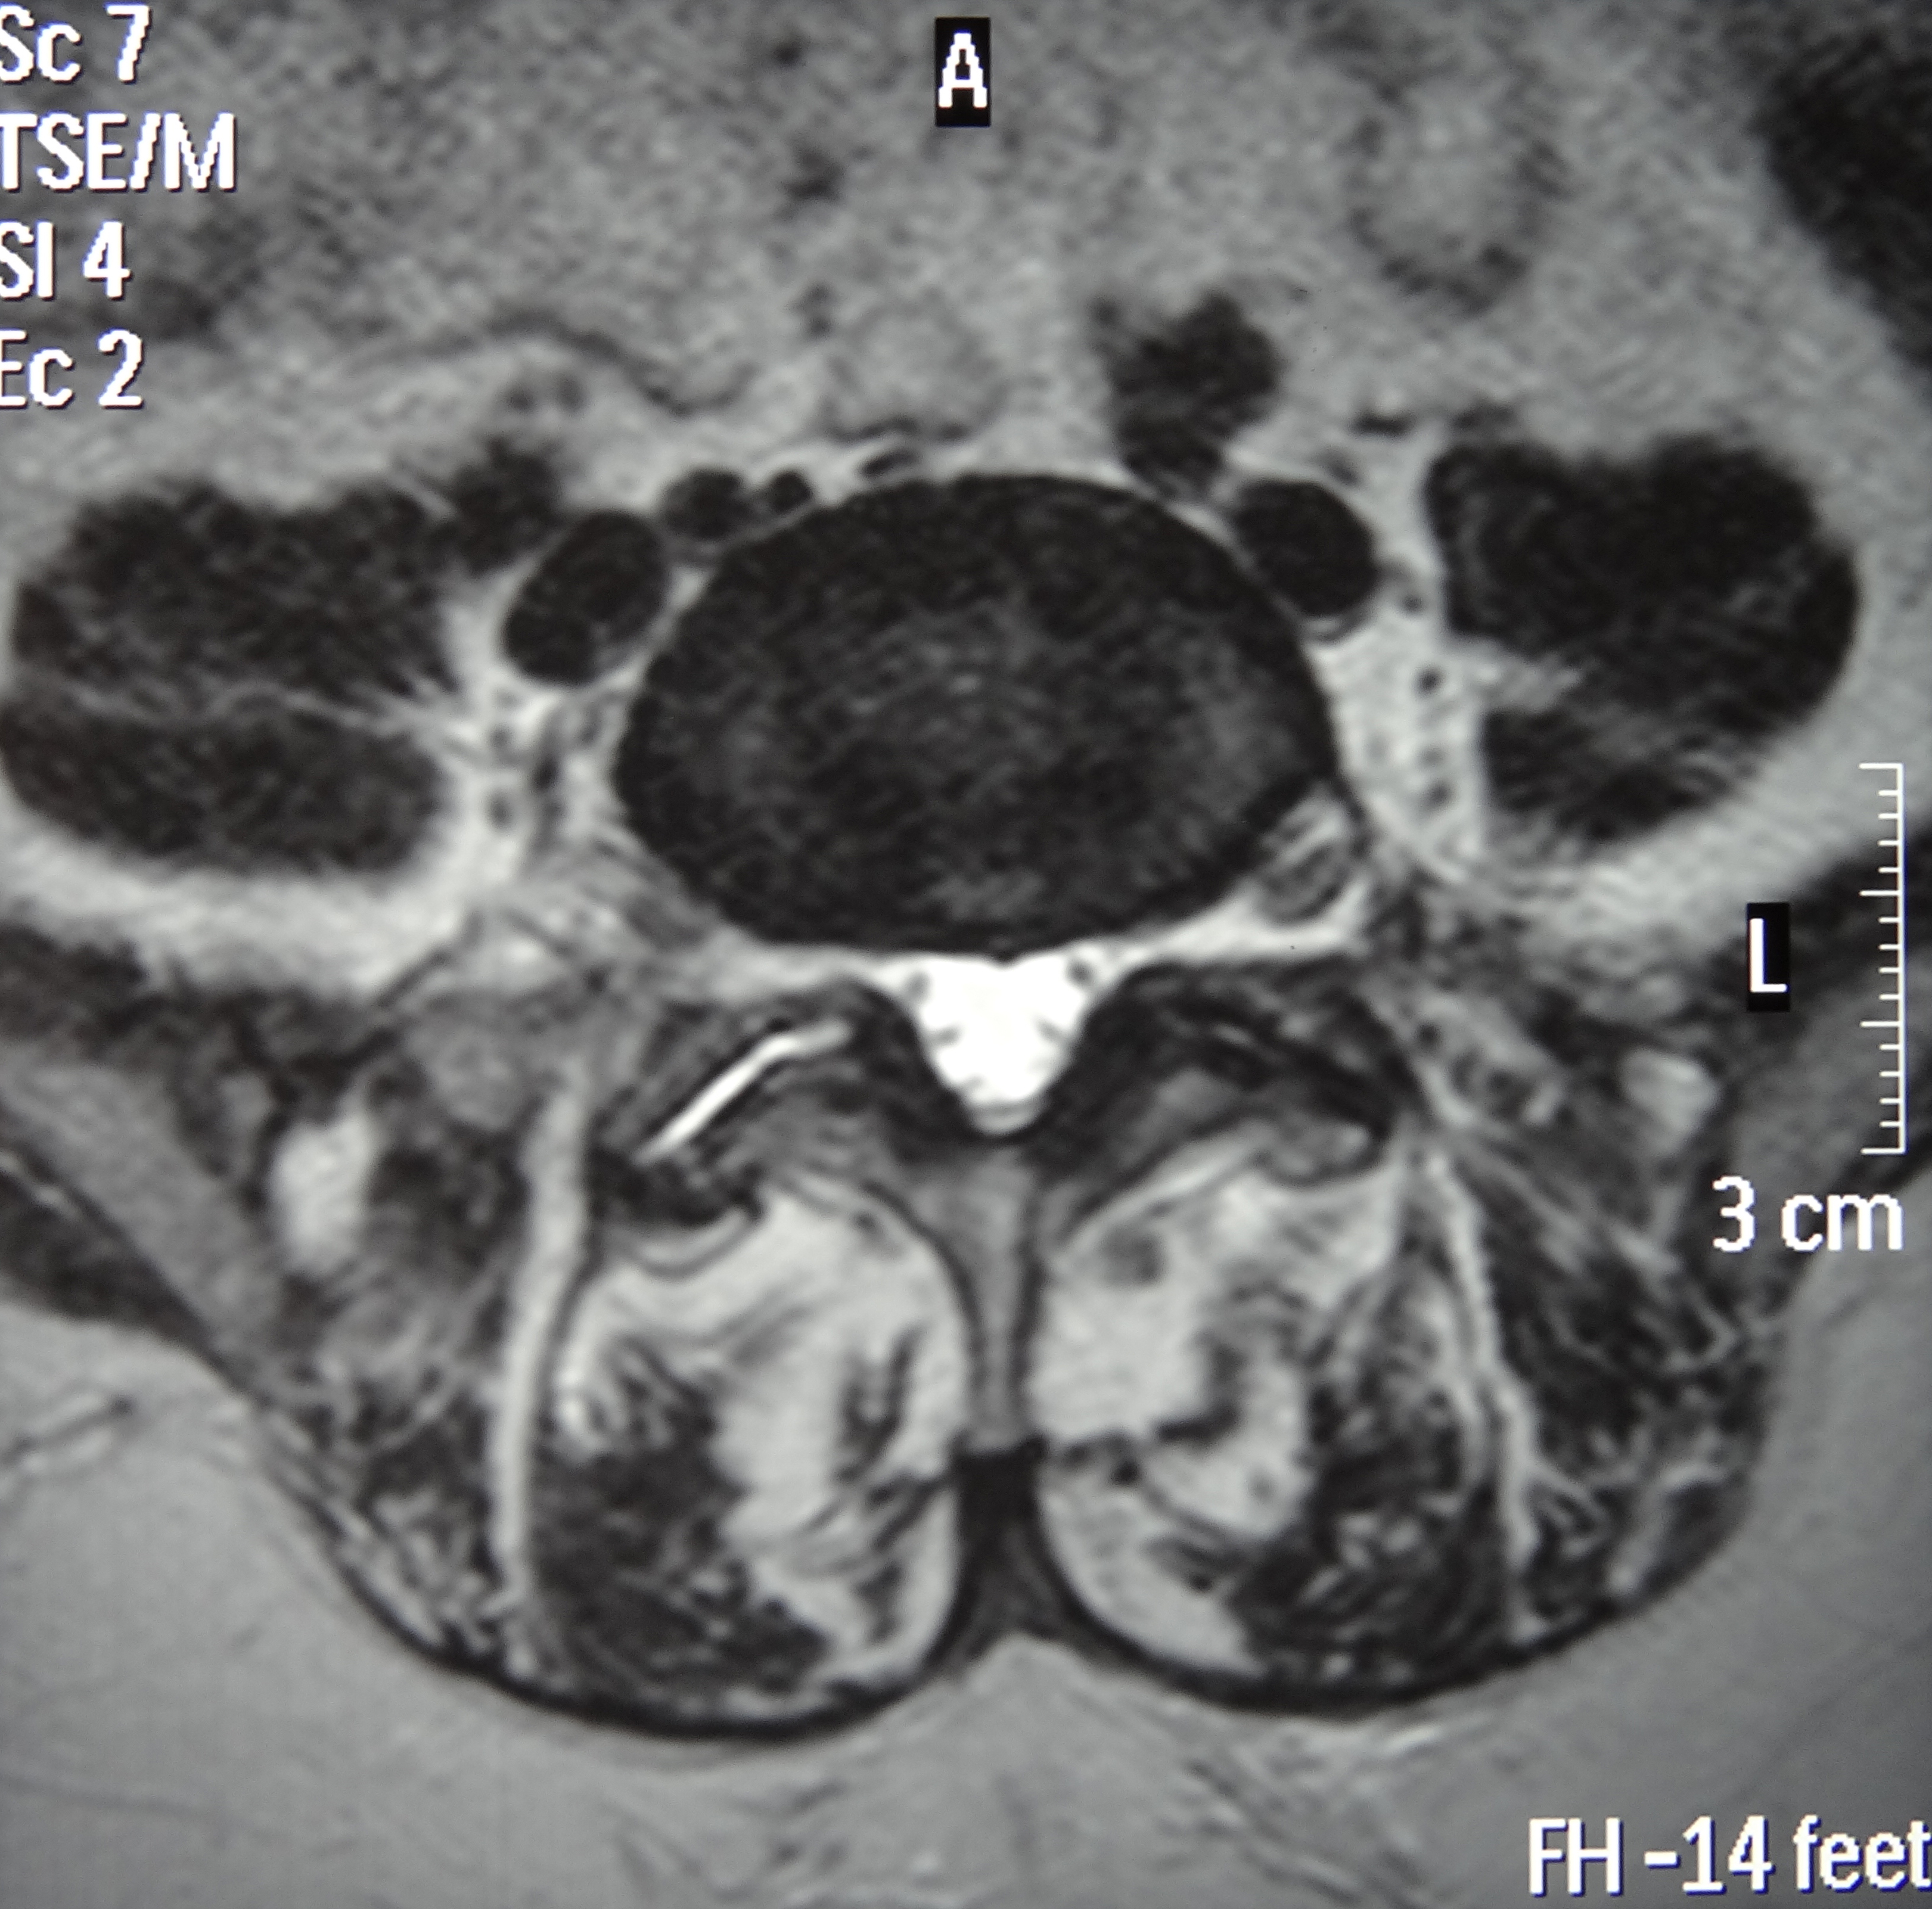

This patient presented with an ultrasound demonstrating a baseball-sized Baker's cyst behind the knee. The "after" film was taken 4 months after the 8th treatment of prolotherapy. He is now enjoying being pain and Baker’s cyst free. At three year follow-up, the cyst had not returned.[/toggle_content]